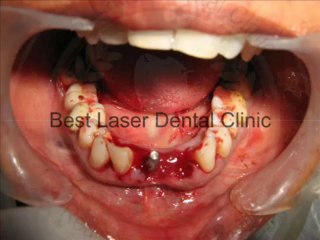

Severe gum abscess tooth extraction and immediate BCS implant placement!